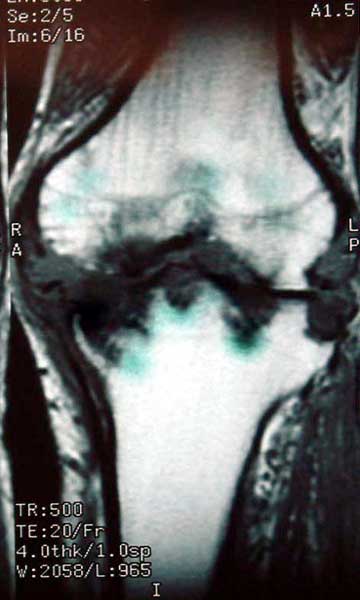

膝关节类风湿关节炎,胫骨近端骨缺损,成蜂窝状    MRI显示骨破坏程度